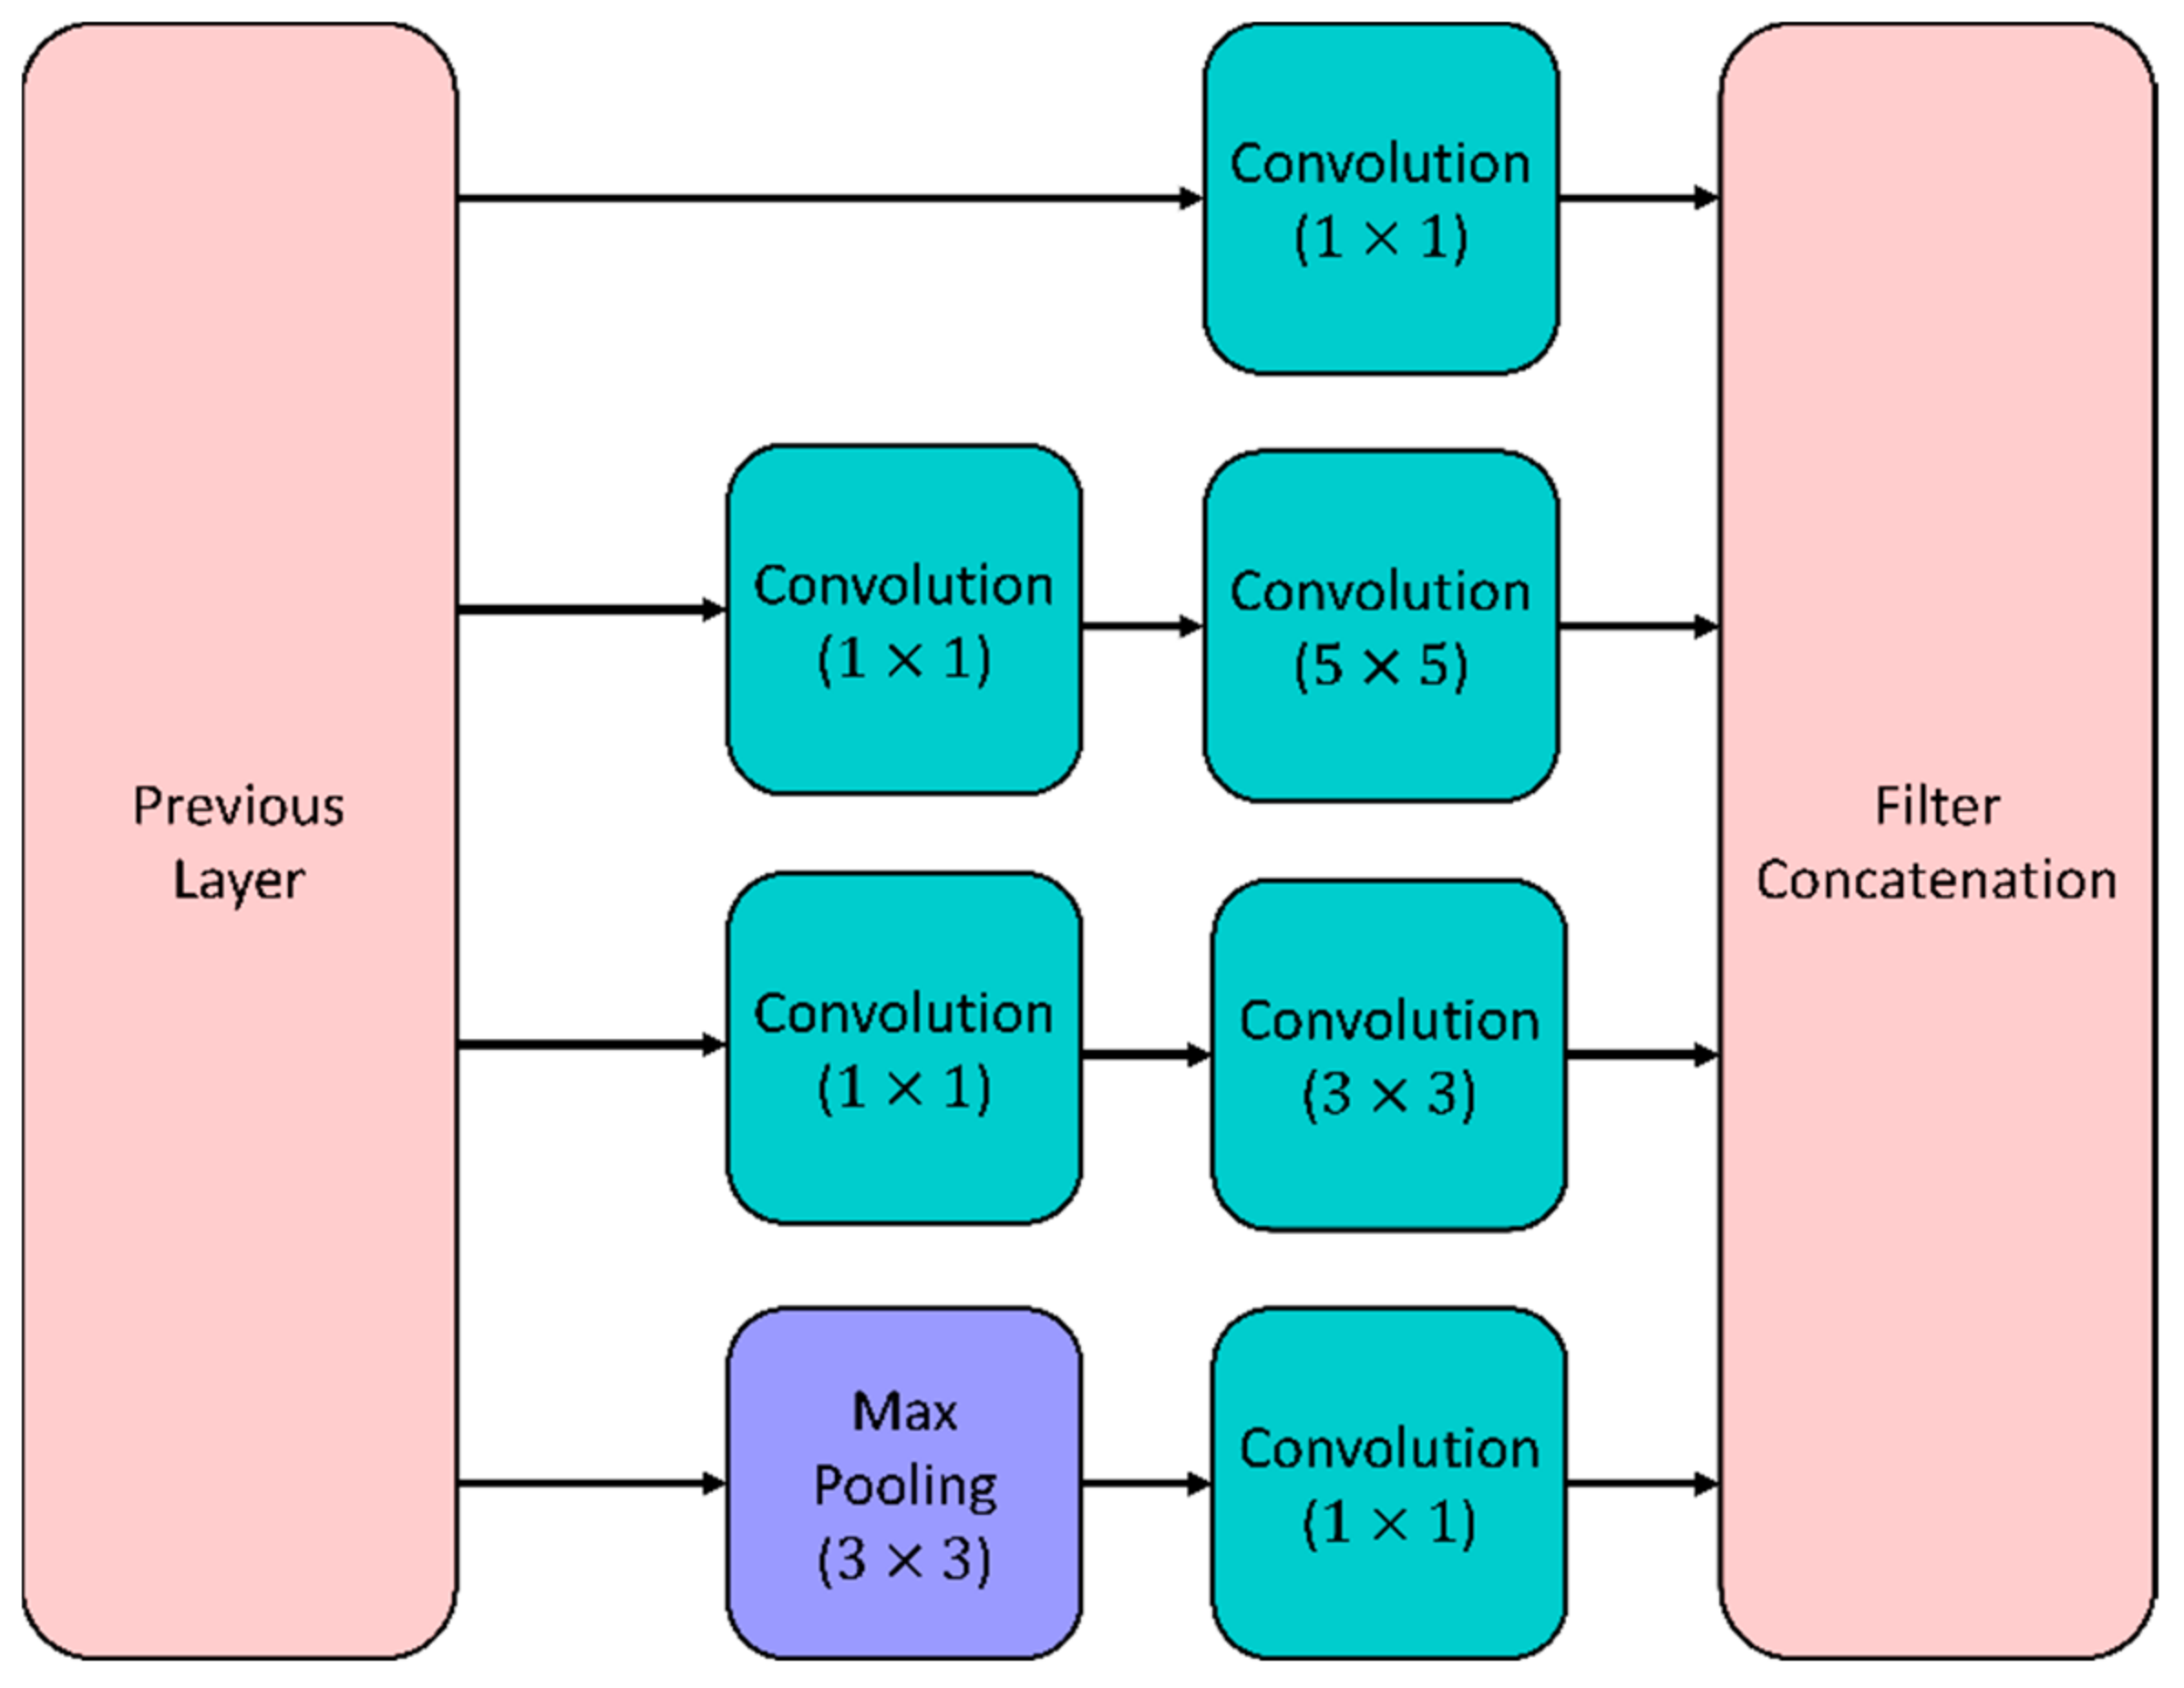

5.1.1. GoogleNet